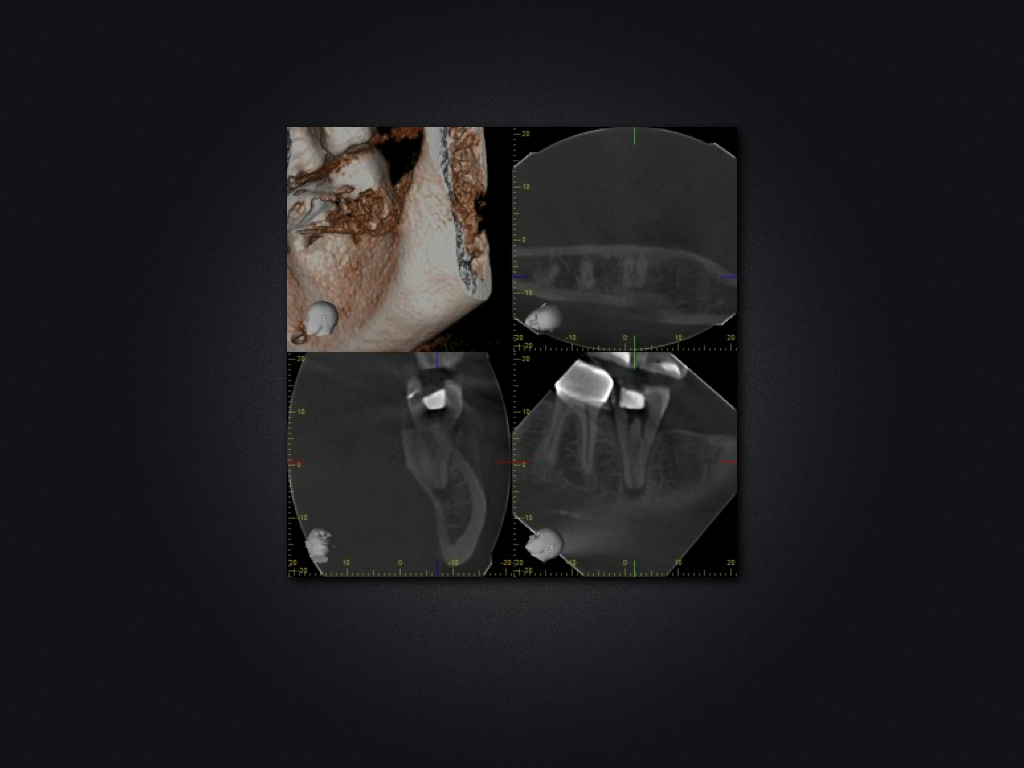

37D.003

37 c-shaped